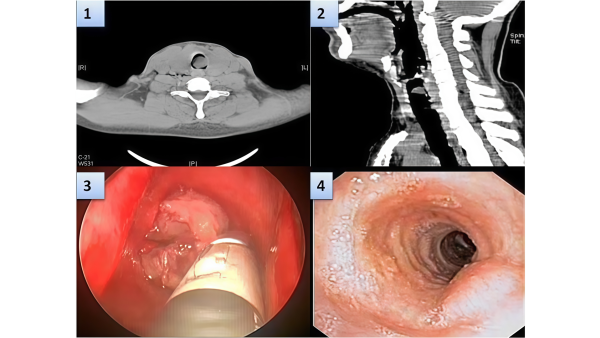

Опубликована запись трансляции проекта Совершенствуйся в ларингологии на тему: «Хронический гиперпластический ларингит». Первая треть записи эфира с